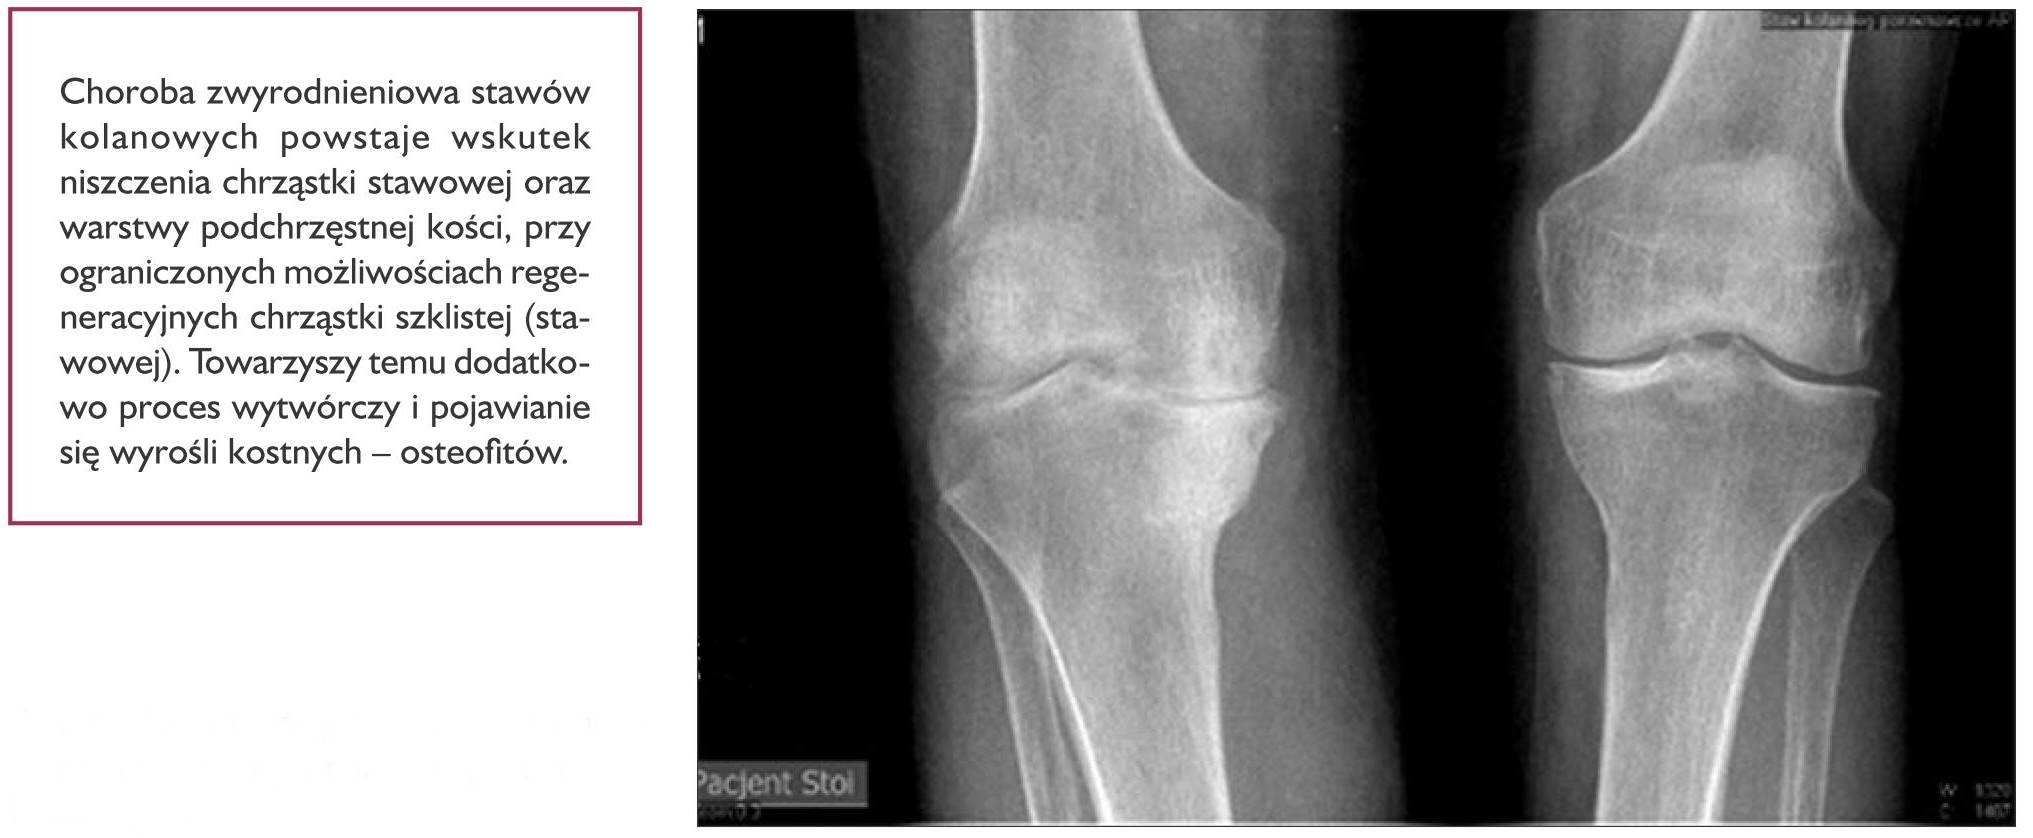

Choroba zwyrodnieniowa stawów kolanowych, zwana także gonartrozą (gonarthrosis), jest obecnie najczęstszą przyczyną niepełnosprawności na świecie (ryc. 4). Wiąże się to ze skomplikowaną budową i mechaniką stawów. Ulegają one przeciążeniom i szybszemu zużywaniu się w przypadku zaburzeń statyki ciała. Gonartroza ma charakter postępujący i obejmuje wszystkie elementy tworzące staw kolanowy, tzn. chrząstkę stawową, warstwę podchrzęstną, błonę maziową, torebkę stawową i więzadła stawowe. Na powstawanie zmian zwyrodnieniowych stawów dodatkowo wpływają takie czynniki, jak wiek, płeć żeńska (zgodnie z danymi Naczelnej Izby Lekarskiej z 4 stycznia 2018 r. w Polsce zawód lekarza dentysty wykonuje 27 671 kobiet i 8978 mężczyzn), siedzący tryb życia, nadwaga, przebyte w przeszłości urazy stawu, zaburzenia hormonalne, a także toczące się przewlekłe procesy zapalne, np. reumatoidalne zapalenie stawów.

Ryc. 4. Zdjęcie rtg. zaawansowanych zmian zwyrodnieniowych stawów kolanowych.